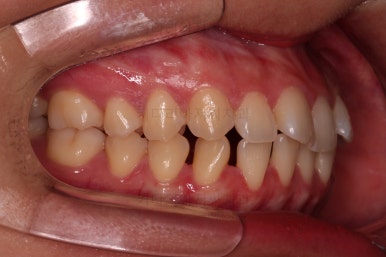

초진 시 입안의 모습입니다.

치열이 많이 삐뚠 것은 아니지만 앞니쪽이 삐뚤어 있고요. 아랫니 사이사이에 고루 틈새가 있네요.

윗니는 삐뚤고(공간부족), 아랫니는 틈새가 있다면(공간 과잉) 그 부조화는 부정교합을 의미합니다.

어금니 교합이 전반적으로 아랫니가 뒤로 빠져있는 교합이어서 맞물림이 좋지 못한 상태였어요.